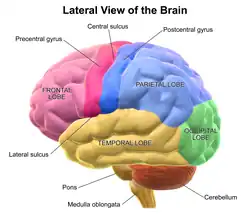

The best example of an established lateralization is that of Broca's and Wernicke's areas, where both are often found exclusively on the left hemisphere. Function lateralization, such as semantics, intonation, accentuation, and prosody, has since been called into question and largely been found to have a neuronal basis in both hemispheres.[6] Another example is that each hemisphere in the brain tends to represent one side of the body. In the cerebellum, this is the ipsilateral side, but in the forebrain this is predominantly the contralateral side.

Speech production and language comprehension are specialized in Broca's and Wernicke's areas respectively, which are located in the left hemisphere for 96% of right-handers and 70% of left-handers.[8][10] However, there are some cases in which speech is produced in both hemispheres in split-brain patients, also lateralization can shift due to plasticity over time.[8] The emotional content of language, called emotional prosody, is right-lateralized.[8]

Broca's aphasia is a specific type of expressive aphasia and is so named due to the aphasia that results from damage or lesions to the Broca's area of the brain, that exists most commonly in the left inferior frontal hemisphere. Thus, the aphasia that develops from the lack of functioning of the Broca's area is an expressive and non-fluent aphasia. It is called 'non-fluent' due to the issues that arise because Broca's area is critical for language pronunciation and production. The area controls some motor aspects of speech production and articulation of thoughts to words and as such lesions to the area result in specific non-fluent aphasia.[25]

Wernicke's aphasia is the result of damage to the area of the brain that is commonly in the left hemisphere above the Sylvian fissure. Damage to this area causes primarily a deficit in language comprehension. While the ability to speak fluently with normal melodic intonation is spared, the language produced by a person with Wernicke's aphasia is riddled with semantic errors and may sound nonsensical to the listener. Wernicke's aphasia is characterized by phonemic paraphasias, neologism or jargon. Another characteristic of a person with Wernicke's aphasia is that they are unconcerned by the mistakes that they are making.

One of the first indications of brain function lateralization resulted from the research of French physician Pierre Paul Broca, in 1861. His research involved the male patient nicknamed "Tan", who had a speech deficit (aphasia); "tan" was one of the few words he could articulate, hence his nickname. In Tan's autopsy, Broca determined he had a syphilitic lesion in the left cerebral hemisphere. This left frontal lobe brain area (Broca's area) is an important speech production region. The motor aspects of speech production deficits caused by damage to Broca's area are known as expressive aphasia. In clinical assessment of this type of aphasia, patients have difficulty producing speech.[38]

German physician Karl Wernicke continued in the vein of Broca's research by studying language deficits unlike expressive aphasia. Wernicke noted that not every deficit was in speech production; some were linguistic. He found that damage to the left posterior, superior temporal gyrus (Wernicke's area) caused language comprehension deficits rather than speech production deficits, a syndrome known as receptive aphasia.